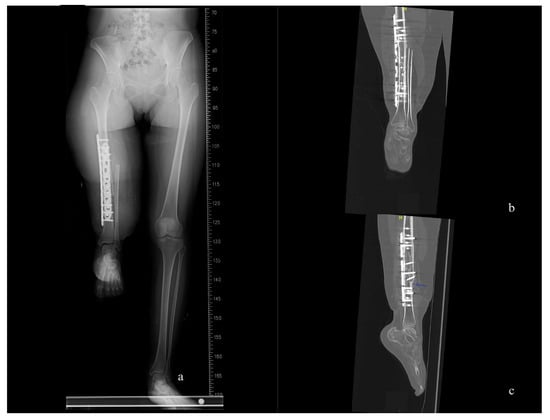

Figure 3.

The position of the right “new knee” is appropriate. (a) Whole-leg axis radiographs at the two-months follow-up. (b,c) CT scans were conducted at the twelve-month follow-up, revealing complete healing of the bone union site and a straight alignment of the leg axis in coronal and sagittal view.